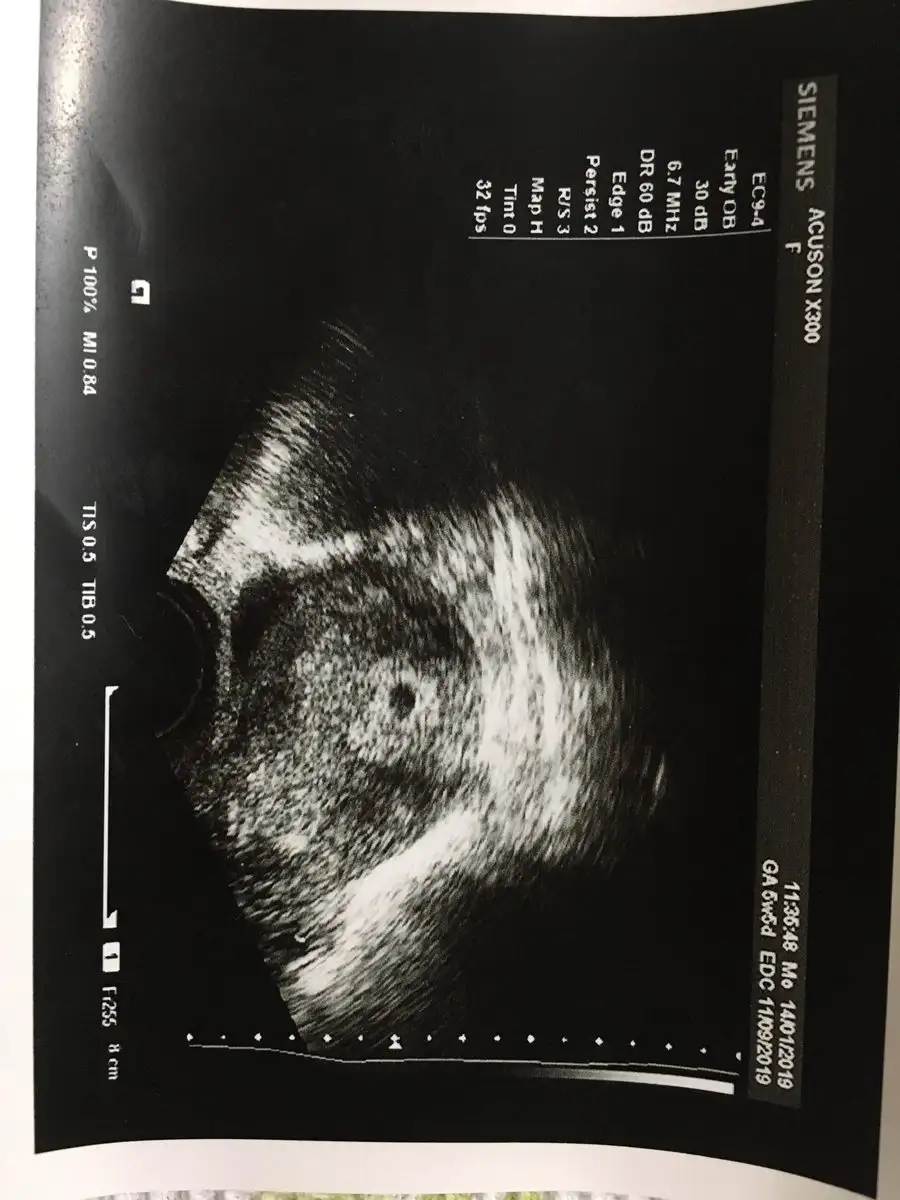

cok sukur cnm gordum bende ama boyutunu olcmedi. Hayirli olsun senindeKızlar şükürler olsun bugün kesemizi gördük 8.5 mm lik kese boyutu çok mutluyum darısı bütün isteyenlerin basınahilal1907 canım sen ne yaptın gittin mi sende kese kontrolüne

Sağol canım seninki de hayırlı olsun boyutu ultrason kagıdında alt ta kösede yazıyor bak istersencok sukur cnm gordum bende ama boyutunu olcmedi. Hayirli olsun seninde